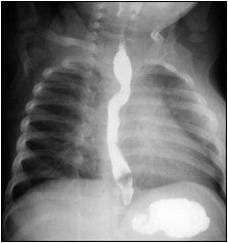

Quiz #6: Barium Swallow Study

Esophagogram:

1) Describe the finding.

2) What is the diagnosis?

Additional "bonus" questions:

3) What tracheal anomaly is associated with this condition?

4) What is the common cardiac defect associated with this condition?